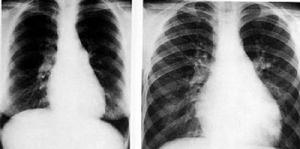

典型的X線表現常有診斷價值,包括三種變化:①與肺葉或段無關的滲出陰影,主要分布在兩肺外側,呈進展性;②使用腎上腺皮質激素後滲出灶迅速吸收;③隨著臨床症狀的反覆滲出亦反覆出現。

診斷常依靠典型的病史以及X線表現。本病應與肺結核、何杰金病等鑑別,如對診斷有懷疑,應爭取肺活檢或支氣管肺泡灌洗檢查,有時也可套用腎上腺皮質激素作診斷性治療。